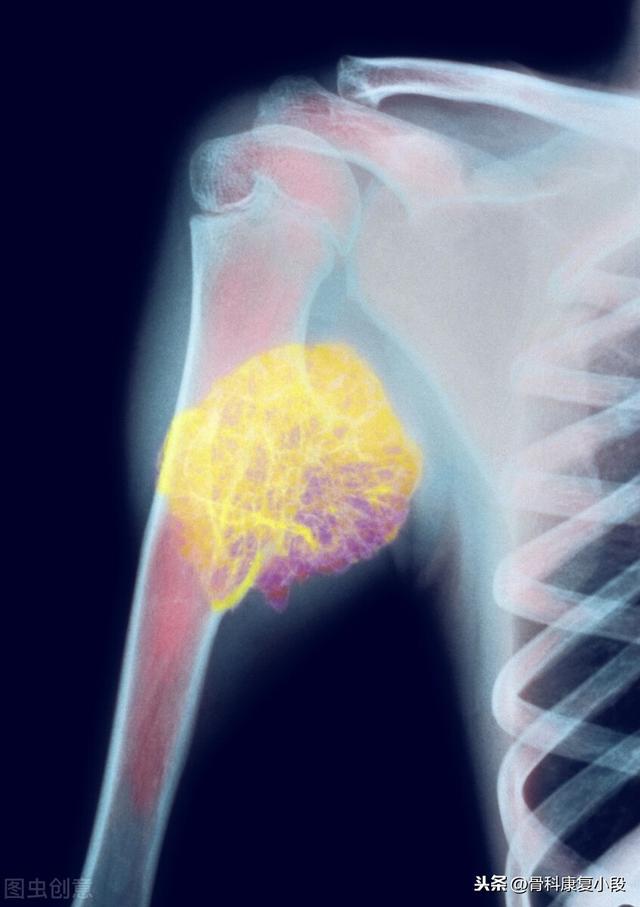

Schlüsselbeinmetastase eines schlecht differenzierten Karzinoms, das seit 5 Jahren mit dem Tumor überlebt hat

Es handelt sich um einen 58-jährigen schwulen Mann, der bei einer leichten Streckung seiner Schulter anhaltende Schmerzen verspürte und bei Röntgenaufnahmen hypodense Herde feststellte:

Es handelte sich um eine pathologische Fraktur, die durch geringe äußere Kräfte auf der Grundlage einer Knochenmetastase verursacht wurde. Es wurde eine Punktion durchgeführt und die Pathologie war eine Knochenmetastase eines schlecht differenzierten Lungenadenokarzinoms.

Was sind die Symptome, die bei Knochenmetastasen auftreten können? Das erste Symptom ist der Schmerz. An der Stelle der Knochenmetastase treten aufgrund der Zerstörung des Knochens Schmerzen auf, die anfangs vielleicht keine offensichtlichen Symptome oder intermittierende Schmerzen haben, aber da der Tumor den normalen Knochen fortschreitend zerstört und sich allmählich verschlimmert, werden auch die Schmerzen an der metastatischen Stelle allmählich stärker. Klinisch gesehen kann es vorkommen, dass wir einen Fall von Knochenschmerzen an einer bestimmten Stelle des Körpers vorfinden, der auf eine Knochenmetastase eines bösartigen Tumors zurückzuführen ist. Vor einiger Zeit traf ich einen Fall, 40 Jahre alt, Schulterschmerzen, dachte, Schultersteife, rieb ein paar Tage der medizinischen Öl nicht sehen Verbesserung, aber mehr und mehr Schmerzen, so ins Krankenhaus zur Untersuchung, hat eine Magnetresonanztomographie, Schulterblatt wurde von einem Stück (Tumor) gegessen, unter Berücksichtigung Knochenmetastasen, und dann hat eine Brust-CT, ein Knoten in der rechten Lunge, und nahm dann eine Biopsie, um die Pathologie, die Knochenmetastasen von Lungenkrebs zu tun war. Die Informationen sind wie folgt.